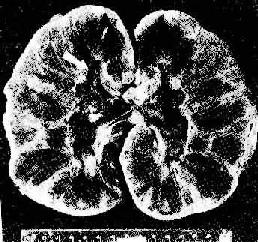

(2)血管型排斥反应:主要为抗体介导的排斥反应(CMC,ADCC和免疫复合物形成),往往在稍后出现,以突出的血管病变为特征。表现为肾细、小动脉的坏死性血管炎,可呈弥漫或局灶性分布。免疫荧光证实有免疫球蛋白、补体及纤维蛋白沉积,肾小球毛细血管袢亦可受累。纤维蛋白样坏死的血管壁内常有淋巴细胞、泡沫细胞及中性粒细胞浸润,腔内可有血小板凝集、血栓形成(图4-5)。后期的血管内膜纤维化,管腔狭窄。间质内常有不同程度淋巴细胞、巨噬细胞及浆细胞浸润。肉眼观,肾常明显肿大,呈暗红色并有出血点,有时可出现黄褐色的梗死灶,可伴有肾盂及肾盏出血(图4-6).临床上,移植肾出现功能减退,大剂量免疫抑制剂疗效不佳。

图4-6 肾移植急性排斥反应

肾肿胀,明显出血,肾盏及肾盂中充满血块